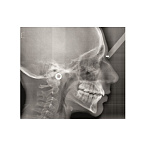

Цифровой панорамный томограф Gendex Pan eXam Plus 2D — это современное и надежное решение для оснащения стоматологической клиники или кабинета. Аппарат предназначен для получения высококачественных двухмерных панорамных снимков зубных рядов, что является основой для планирования лечения, имплантации, ортодонтической коррекции и оценки общего состояния зубочелюстной системы.

- Широкий набор программ сканирования: Аппарат поддерживает различные режимы съемки, адаптированные под конкретные клинические задачи: стандартная панорама, панорама детей, съемка височно-нижнечелюстных суставов (ВНЧС), синус-сканирование и другие.

- Мощное программное обеспечение: В комплекте поставляется интуитивное ПО для управления съемкой, обработки и анализа изображений. Возможности включают в себя масштабирование, регулировку контрастности и яркости, проведение измерений, что облегчает постановку диагноза и консультацию с пациентом.